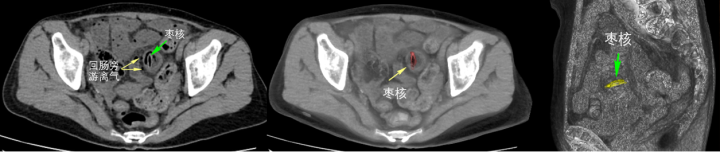

病例四:66岁的祝大妈喝红枣稀饭时失慎吞下枣核,不久后腹痛加重,kaiyun sports检讨发现枣核已穿透肠壁,激发肠穿孔、肠防碍,必须尽快手术骚动。